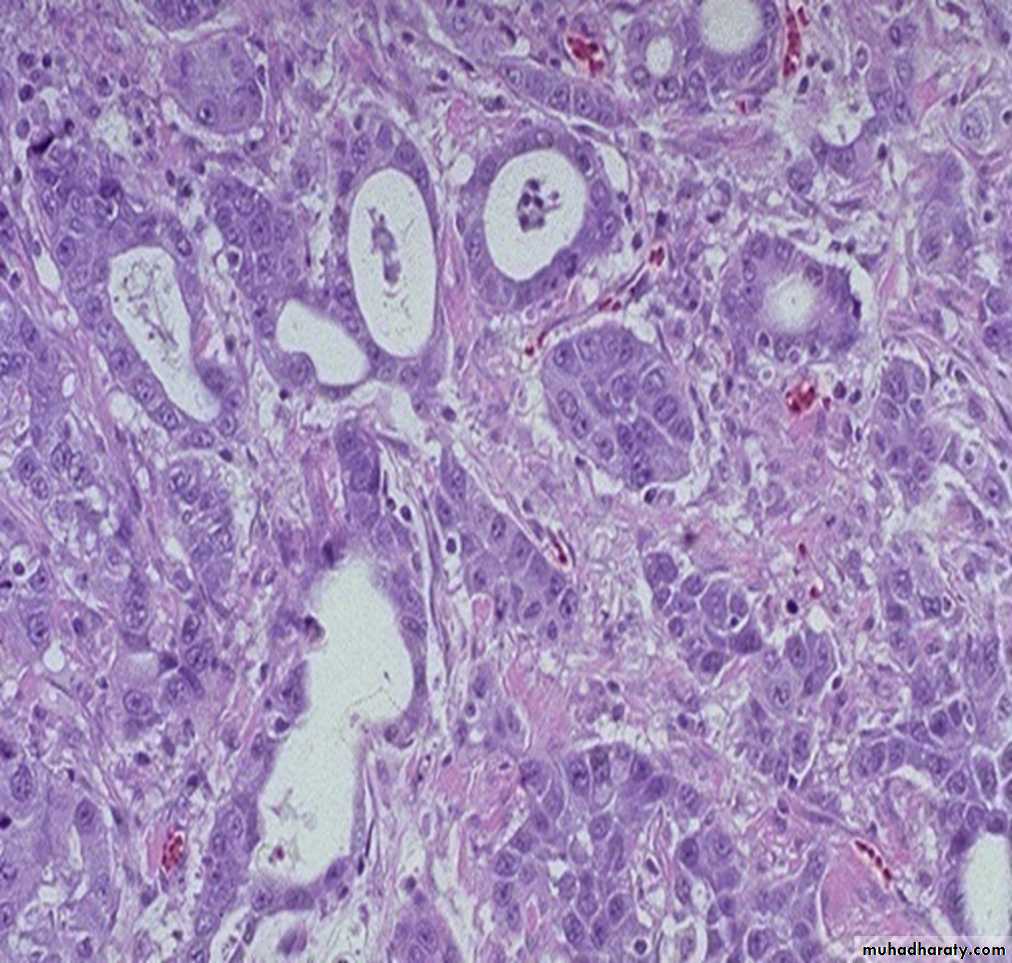

squamous cell carcinoma with a keratin pearl composed of cells with brightly eosinophilic cytoplasm.